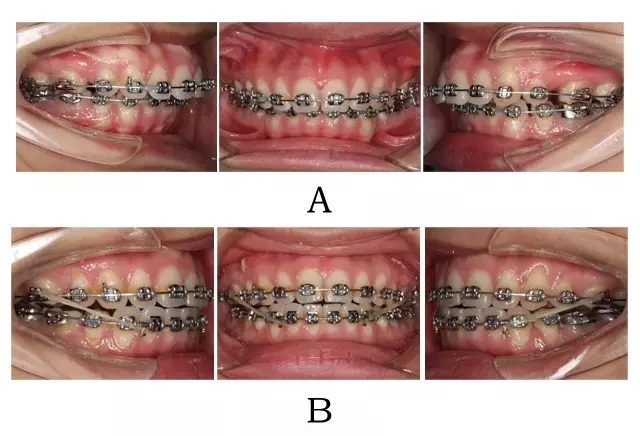

(5)一般選擇拔除上 5 下 4。根據(jù)手術需要,可能也需拔除智齒。術后正畸的主要任務是利用術后新鮮創(chuàng)口的組織反應活躍期,進行上頜內(nèi)收維持與加強、上下頜中線糾正、牙弓進一步整平、覆合覆蓋協(xié)調(diào)及后牙中性關系下的尖窩對接(圖2-2)。

圖 2-2:骨源性突面畸形圍術正畸。(A)術前正畸 (B)術后正畸

Figure 2-2. Orthodontic involvement prior to and following with orthognathic surgery for skeletal prognathism. (A) Pre-operative orthodontics. (B) Post-operative orthodontics.